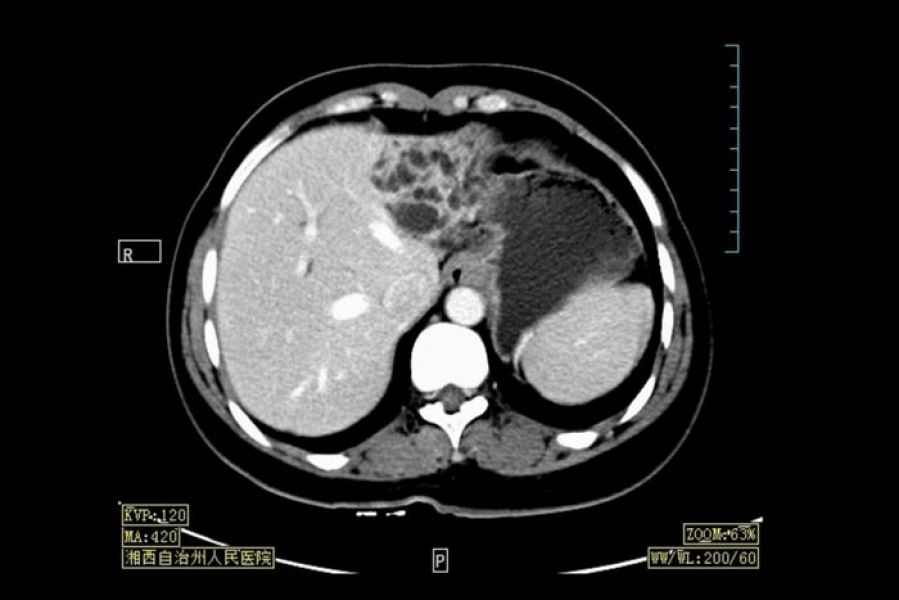

来自贵州松桃的患者吴某某,10月21日以“反复上腹部胀痛10余年,再发并加重5天”为主诉入院。入院后完善增强B超、CT、MRI等影像学检查,诊断为“1、左侧肝内胆管囊状扩张,左肝萎缩,性质待定,考虑良性可能性大;2、胆囊结石,胆囊多发息肉,慢性胆囊炎;3、胆总管扩张”,患者手术指征明确,手术规划:行胆囊切除+左肝切除+胆总管探查术,术中根据左肝标本快速病理切片结果决定是否需行根治性手术。

图1:术前CT片